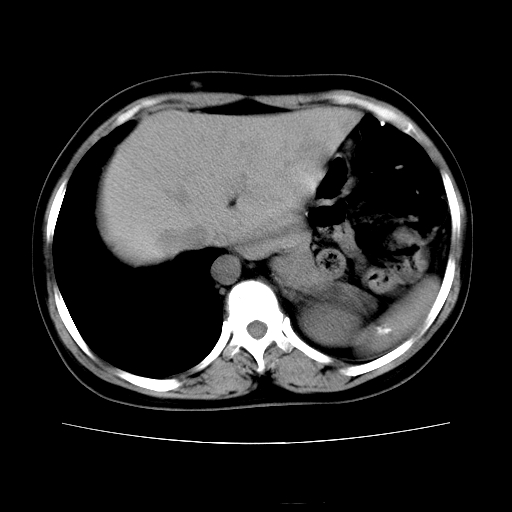

女45y多次(7次)碎石,结果不理想!曾碎石后尿出小碎石,仍腰痛,要求ct,其它不详.本人更倾向于钙化斑!无肾实质破坏,积水等提示集合系统无梗阻.另外腹腔多处钙化.是否结核后改变!谢谢赐教!

1)双肾结石。2)脾脏钙化灶。3)腹膜后多发淋巴结钙化。

尿路结石与腹部淋巴结钙化共存,建议v尿路造影检查,免得钙化灶冤枉为结石受罚。

考虑双肾结石,肾脏实质无破坏表现,没有结核病史,不考虑肾结核,